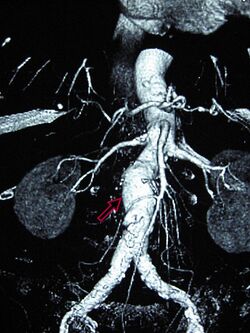

A 6.5 cm AAA with a 3 cm lumen

An aortic aneurysm can occur as a result of trauma, infection, or, most commonly, from an intrinsic abnormality in the elastin and collagen components of the aortic wall. While definite genetic abnormalities were identified in true genetic syndromes (Marfan, Elher-Danlos and others) associated with aortic aneurysms, both thoracic and abdominal aortic aneurysms demonstrate a strong genetic component in their aetiology.[14]